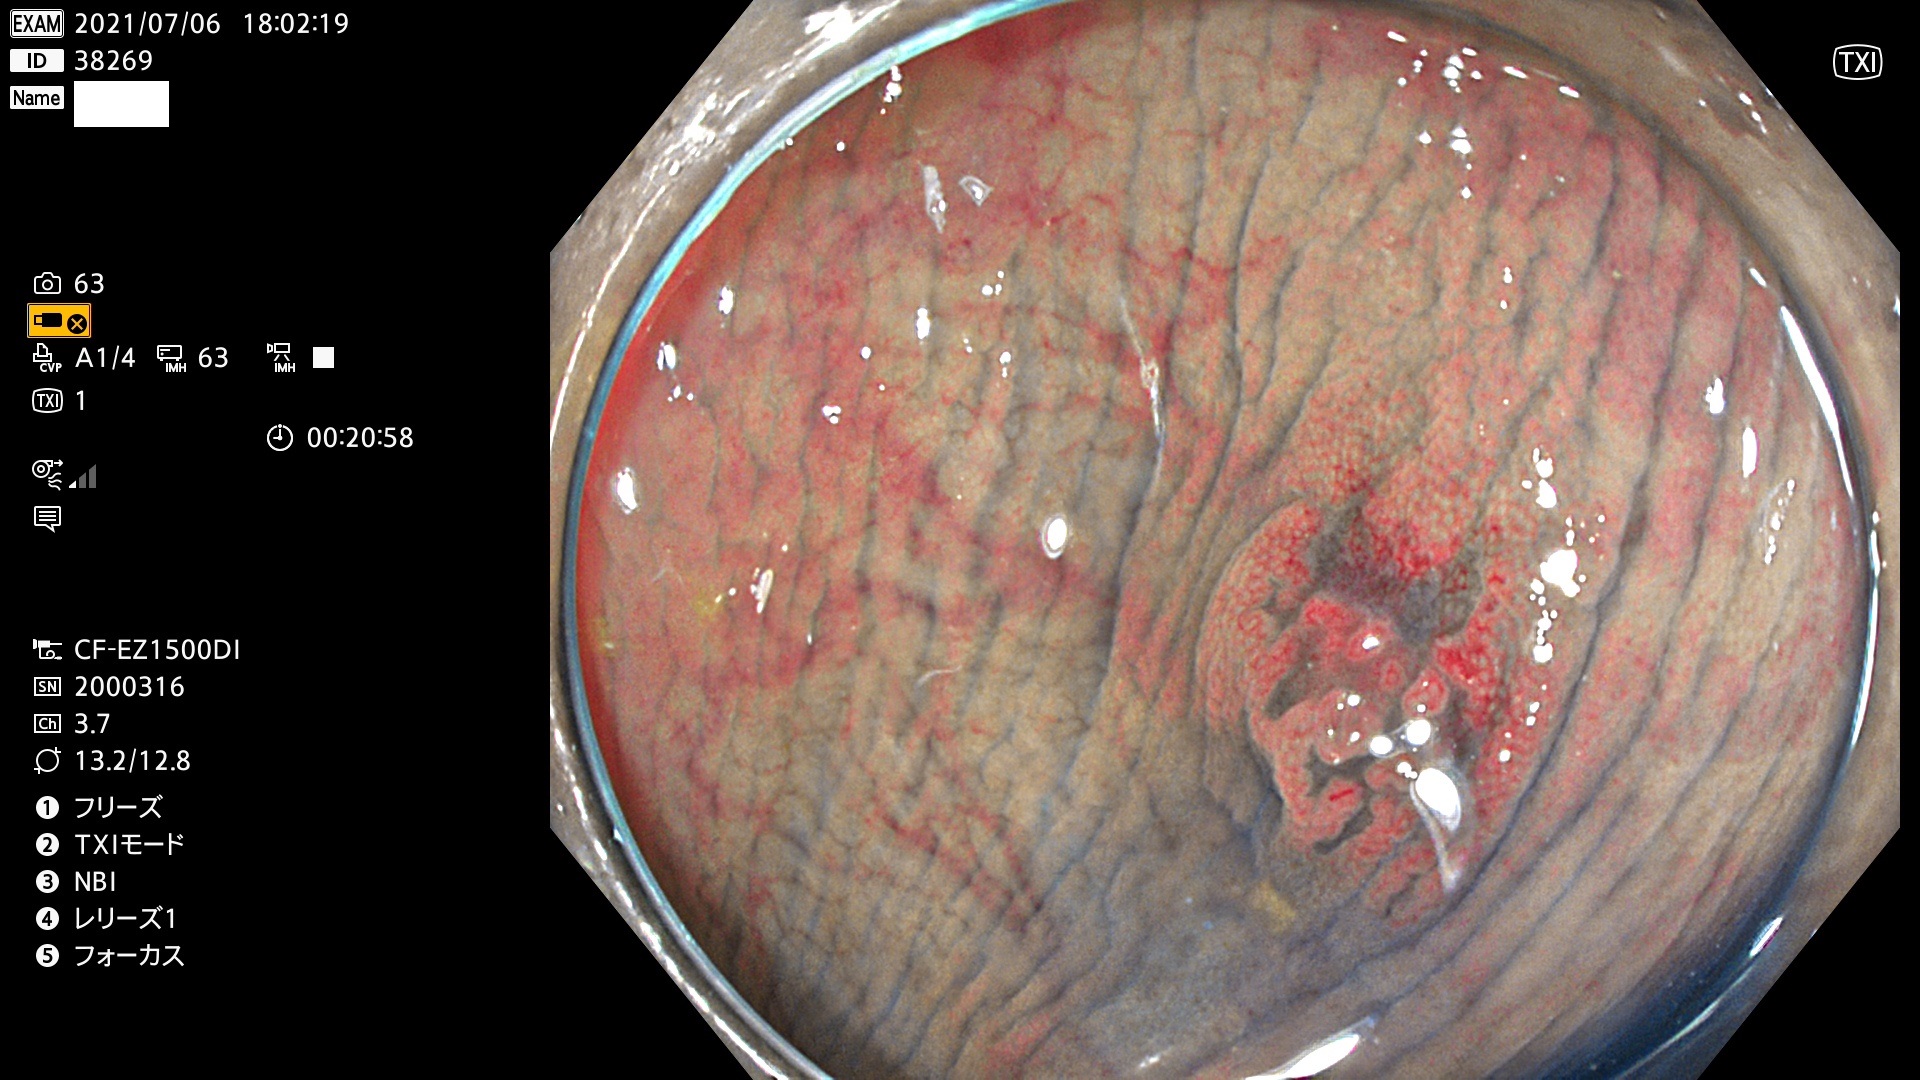

38200 38201 38202 38203 38204 38208 38209 38210 38211 38212 38213 38214 38215 38219 38220(SSAPのみ) 38221 38225 38226 38227 38228 38229 38230 38231 38232(SSAPのみ) 38233 38234 38235 38237 38238 38239 38240 38241 38242 38244 38245 38246 38247 38248 38249 38250 38251 38252 38253 38254 38256 38257 38258 38259 38260(SSAPのみ) 38262 38265 38267 38268(SSAPのみ) 38269 38270 38272 38273 38274 38276 38278 38280 38281 38282 38283 38284 38287 38288 38289 38290 38291 38292 38295 38296 38297 38298 38299(SSAPのみ)

発見困難で危険性の高い平坦型病変(上記100名より抽出)